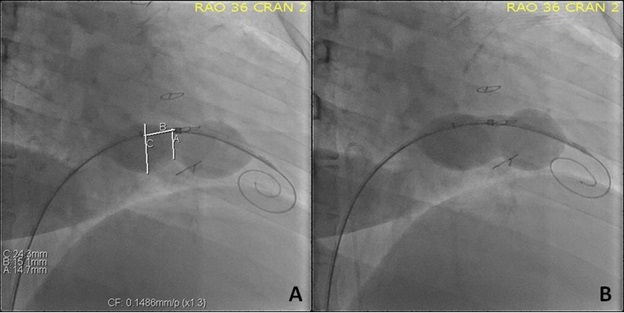

Under conscious sedation, access was obtained in the right femoral vein with an 8 French (Fr) sheath and in the right femoral artery with a 5 Fr sheath. The patient received 2 g of Cefazolin and 10 000 units of unfractionated heparin intravenously, achieving an activated clotting time of 292 seconds. A 7 Fr balloon wedge catheter (Teleflex Medical) was used to exchange for a soft J-tip exchange length wire. We then placed a Langston 6 Fr dual-lumen pigtail catheter (Vascular Solutions) to take simultaneous gradients across the tricuspid valve. The mean diastolic gradient was 10 mm Hg with a right atrial mean pressure of 25 mm Hg (Figure 2A). A modified Safari Extra Small wire (Boston Scientific) was then introduced in the right ventricle, and a 34-mm AGA sizing balloon (AGA Medical Corporation) was placed across the TV. Upon inflation, we only noted a waist at the level of the leaflet tips measuring 15 mm on a calibrated measurement. Though the balloon was inflated up to 24 mm proximally, the annulus could not be delineated (Figure 3A).

Given this and the TEE measurements, we decided to start with a 20 mm x 5-cm Z-Med II-X balloon (B. Braun Interventional Systems). Using a hand inflation estimated at less than 2 atmospheres twice (10 seconds each), the waist dilated easily. The balloon was removed, and both echocardiographic and hemodynamic assessments were performed. The right atrial mean pressure dropped to 23 mm Hg, and the mean diastolic gradient across the TV was 7 mm Hg by both modalities (Figure 2B). There was no significant regurgitation. We then introduced a 22 mm x 5-cm Z-Med II-X balloon (B. Braun Interventional Systems) and dilated it again at a similar pressure twice (10 seconds each). Post-inflation assessments showed a right atrial mean pressure of 24 mm Hg with a mean diastolic gradient of 6 mm Hg by cath and 5 mm Hg by transthoracic echocardiogram (TTE) (Figure 2C). There was trivial regurgitation. We then repositioned the sizing balloon within the valve annulus. On inflation, the valve leaflet tip opening was 20 mm, as was the annulus (Figure 3B).

Once the anatomy was defined, we advanced an AGA sizing balloon (AGA Medical Corporation). Balloon inflation showed a 12-mm waist at the tips of the tricuspid valve leaflets (Figure 6A). Given these findings and the data from the CT, we decided to advance a 22 x 5-cm Z-MED II balloon (B. Braun Interventional Systems) and performed an inflation with a clear improvement in the waist. However, we only were able to measure 16 mm of leaflets excursion. Then, we advanced a 25 x 5-mm Z-MED II balloon (B. Braun Interventional Systems) and performed another inflation, which further dilated the annulus (Figure 6B). We then used a Langston dual-lumen pigtail catheter (Vascular Solutions) for simultaneous pressure measurement. The mean gradient was 6 mm Hg, with similar values obtained by TTE.